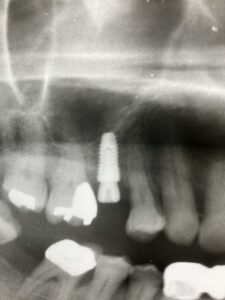

インプラントの上部構造の最終補綴物にメタルボンドと呼ばれるセラミックが使用されていました。今でも使用しますが1番の欠点として破折の可能性があることです。近年、物性や神秘性が格段に向上したジルコニアが、第一選択上がるようになりました。